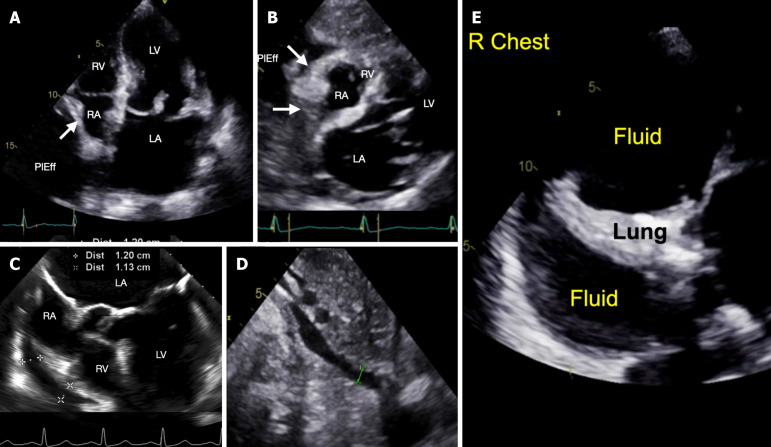

Case summary: A 74 year-old woman with severe MR, a left ventricular ejection fraction of 45%, and a small circumferential pericardial effusion underwent TEER of the mitral valve. After the placement of two MitraClips, the MR was assessed as mild to moderate. Within 10-20 minutes after the completion of the case, the patient was dyspneic and hypotensive despite volume resuscitation. Point-of-care ultrasound (POCUS) showed no changes in cardiac contractility, valve function, or the pericardial space. The right heart chambers appeared small with right atrial (RA) diastolic collapse. There was no evidence of venous congestion. Further exam showed a large right pleural fluid collection. Given the clinical scenario of dyspnea, hypotension, and diastolic RA collapse, low-pressure tamponade was suspected. A thoracentesis expelled 1200 mL of blood with immediate hemodynamic improvement. The patient made an uneventful recovery.

Conclusion: The application of POCUS is crucial for detecting, diagnosing, and properly managing cardiac dysfunction and procedural complications associated with TEER. While tamponade is classically associated with a pericardial effusion and vena caval plethora, their absence does not dismiss the suspicion or diagnosis of tamponade. This case highlights the value of POCUS in assessing low-pressure tamponade caused by a large, pressurized pleural effusion. Clinical suspicion, supported by POCUS findings, was confirmed by a thoracentesis that resulted in immediate hemodynamic improvement.